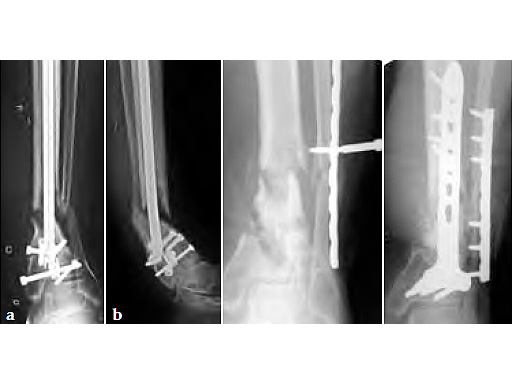

Case provided by Phil Kregor, Nashville, USA.

31-year-old male with a 2.5-year history of a distal tibial nonunion/malunion with three previous surgeries. Significantly compromised soft-tissue envelope anteriorly.

Removal of the intramedullary nail followed by posterior iliac bone grafting and plate fixation of both the fibula and tibia. A posterolateral approach was used to approach both the tibia and the fibula. The posterior locking T-plate was used for fixation of the tibia.

Some residual varus deformity of the tibia remains, but clinically the patient is full weight bearing and has returned to work after 4.5 months.